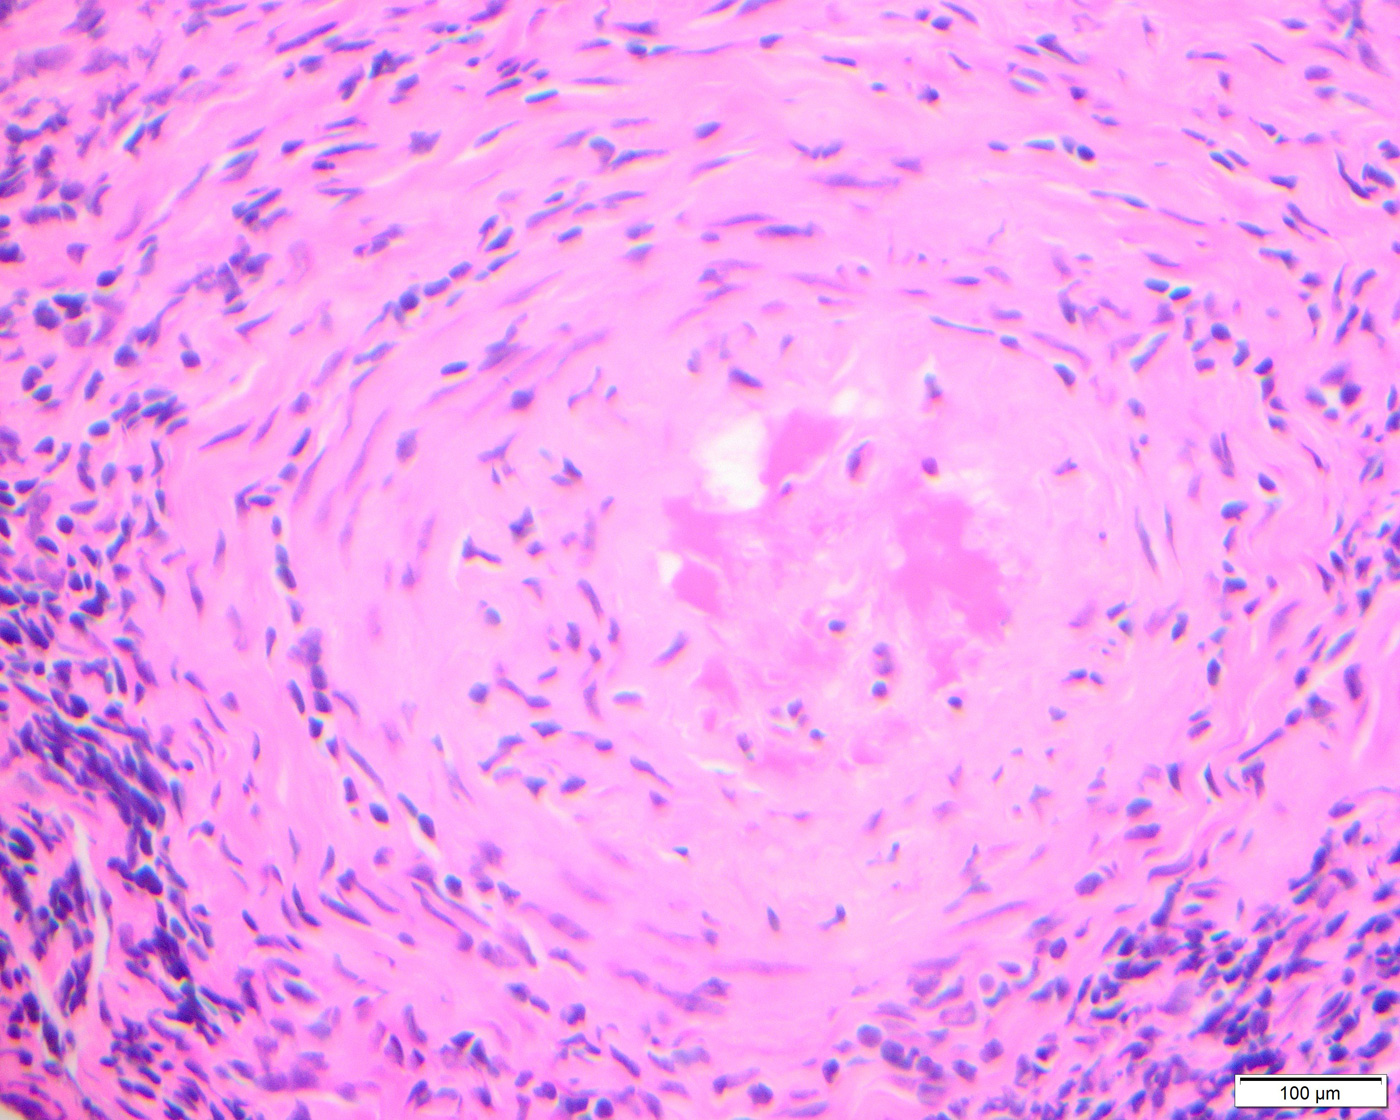

Histologic sections of the debrided tissue showed extensive necrosis of the sinonasal mucosa, soft tissue, and cartilage, abundant mixed inflammatory cells, and fungal organisms with features compatible with vascular invasion (Fig. 1). Intravascular thrombi (Fig. 1) and calcium oxalate crystals (Figs. 2 and 3) were also identified. The fungi were highlighted by GMS stain (Figs. 4 and 5) and displayed unpigmented septate acute-angle branching hyphae (Fig. 6) and fruiting bodies (fig. 7). Another fungal organism with wider hyphae, morphologically suggestive of Fusarium or Scedosporium was seen (Fig. 8). However, since no other fungi were isolated from culture, its exact identification remains unconfirmed.